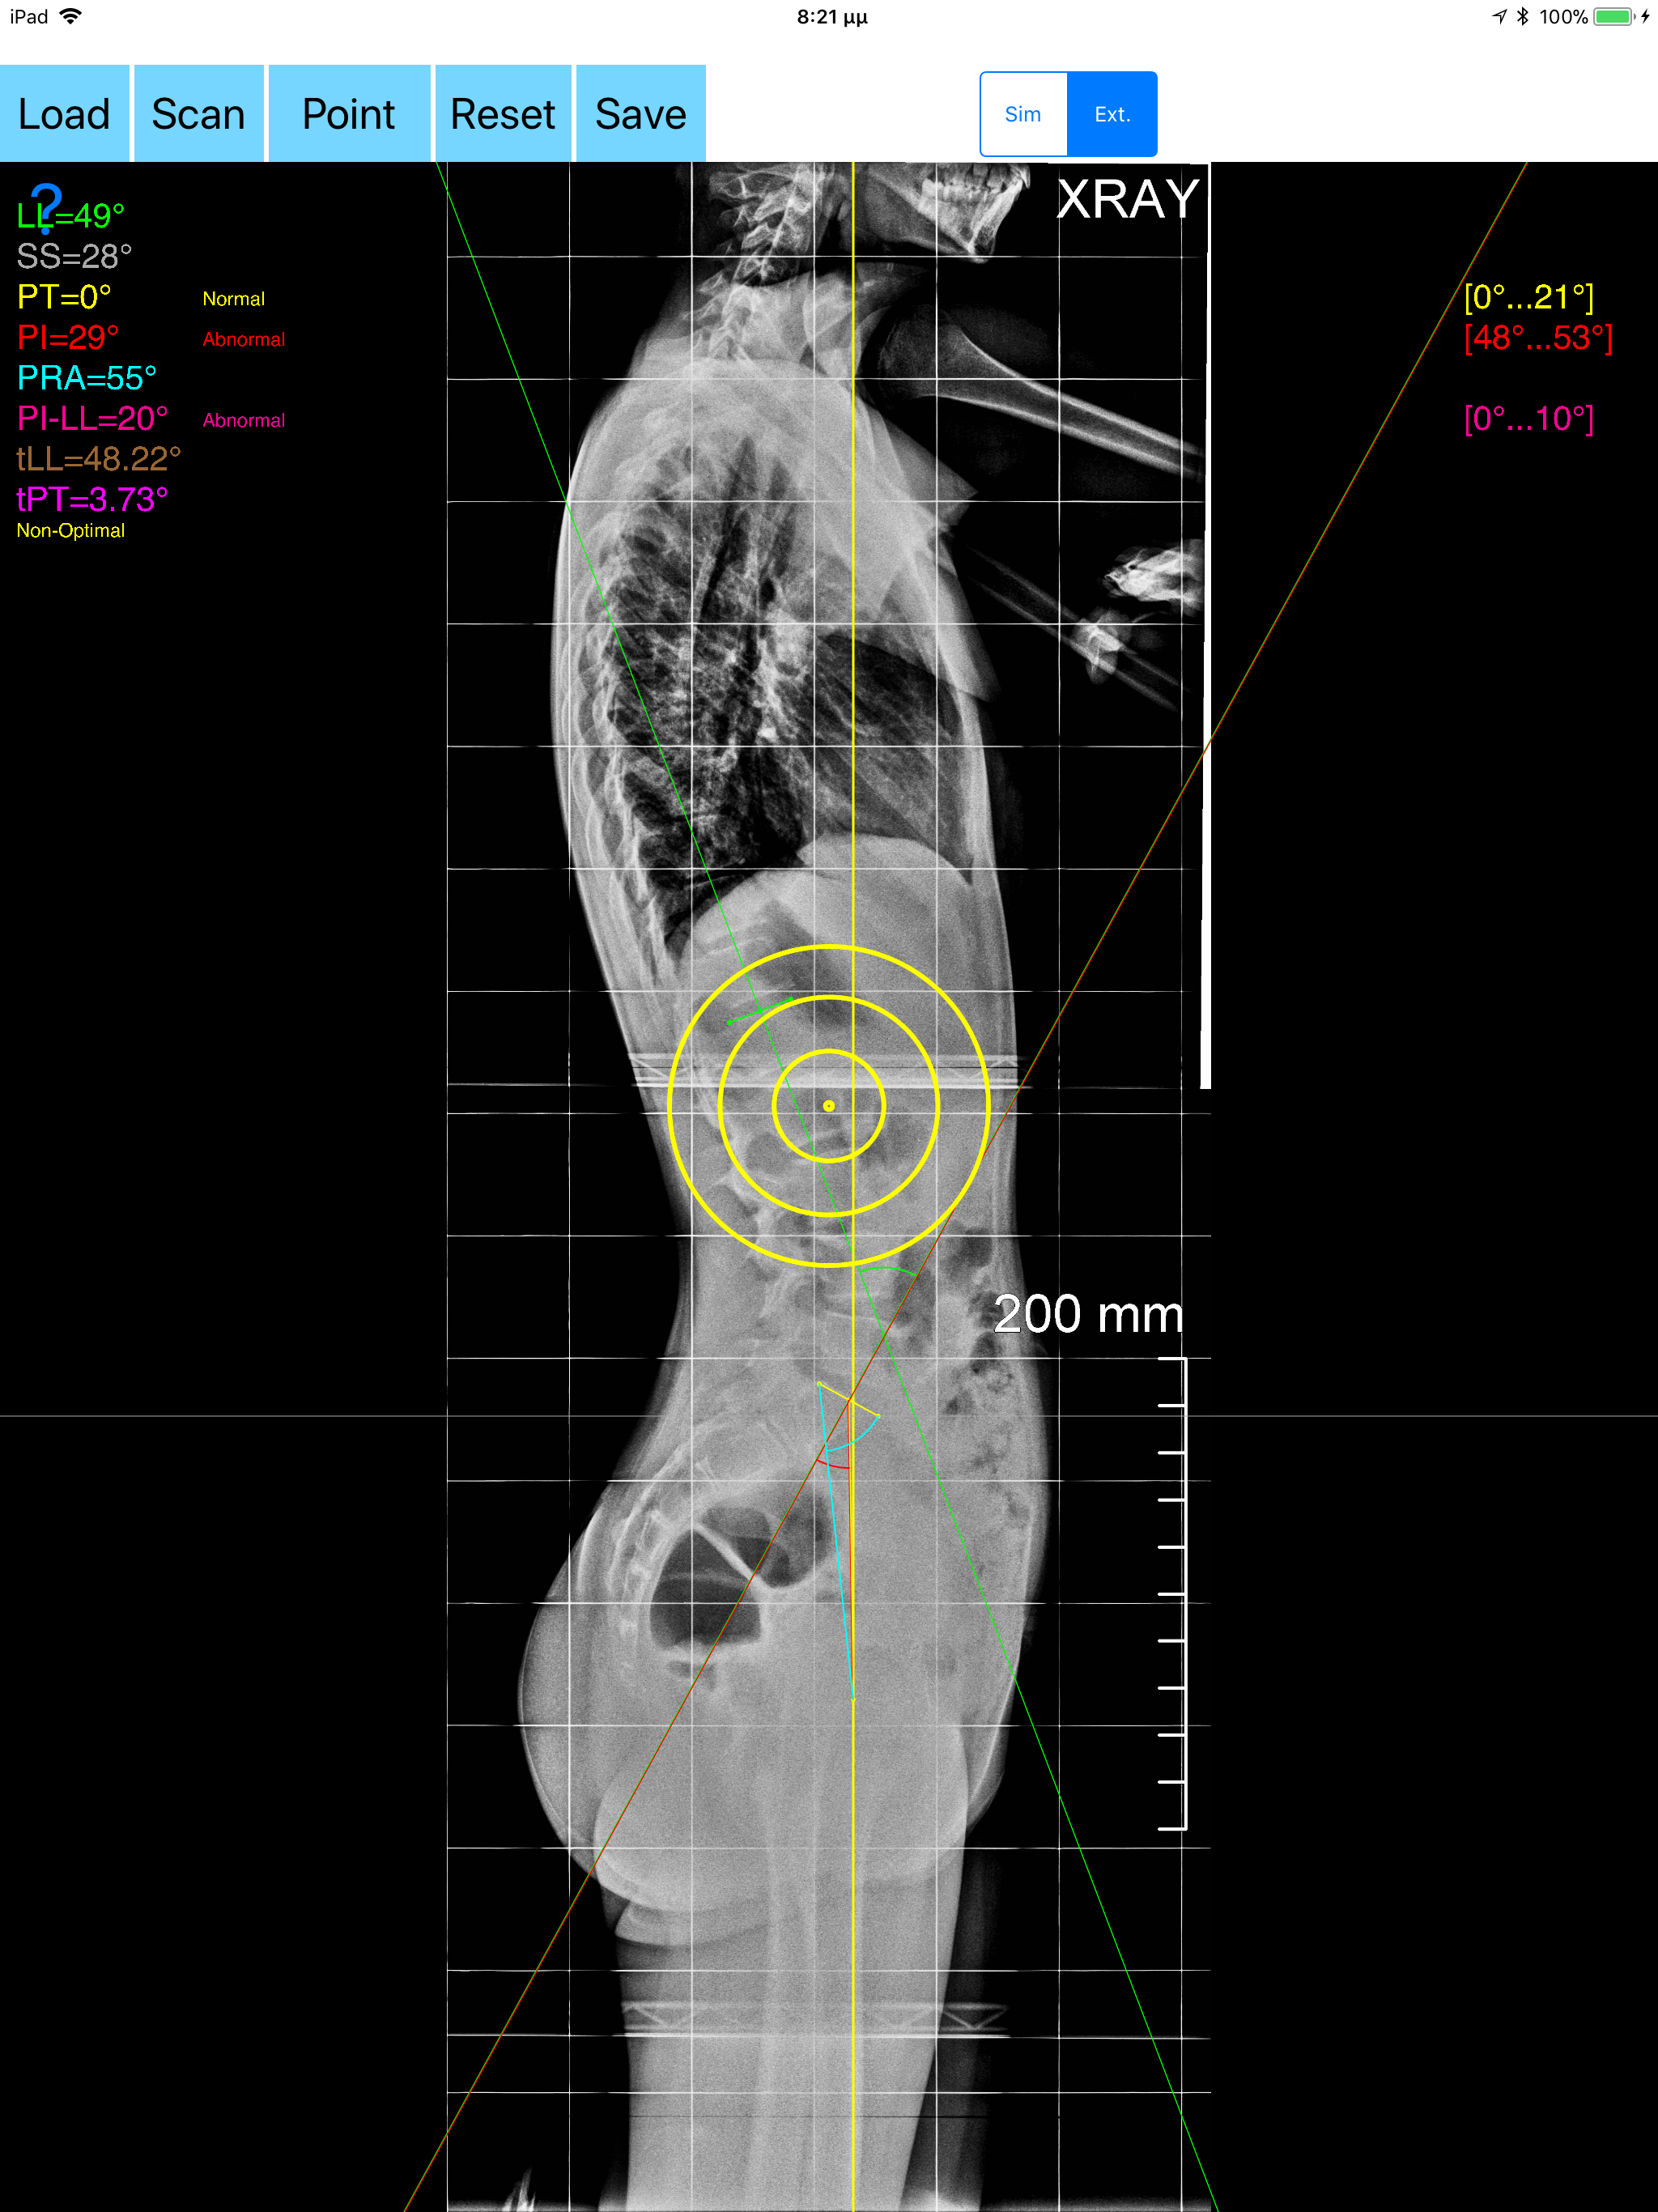

The assessment of the parameters involved in spinopelvic jucture are of paramount importance for spine and joint replacement surgeon. The dynamic interplay between flexibility and balance around the axis of gravity determine the type and the amount of influence in spine and hips. Radiographic parameters to evaluate objectively the spinopelvic sagittal balance are Pelvic incidence (PI), Sacral slope (SS), Pelvic Tilt (PT), Lumbar lordosis (LL). Drawings in patients X-rays and precise measurements are important in order to quantify the magnitude of spinal deformities, to monitor the success or failure of treatment and thus optimise the management of patients according to the severity of the imbalance or even to identify patient at risk of degenerative spondylolisthesis or disk herniation. The Spinopelvic Balance App is medical software aimed for orthopaedic surgeons, providing tools that allow doctors to: -Securely import medical images directly from the camera or stored photos. -By marking few points at the image of X-ray, the App calculates and offers a very convenient way to determine the most accurate possibly way at once, Pelvic incidence (PI), Sacral slope (SS), Pelvic Tilt (PT), Lumbar lordosis (LL), thoracic kyphosis, PI–LL Pelvic incidence Angle (PI) minus Lumbar lordosis Angle (LL) PI–LL, theoretical normal pelvic tilt (tPT),theoretical normal L1-S1 lumbar lordosis (tL1S1), Pelvic Radius Angle (PRA). According to measured parameters the app categorises the severity of the imbalance of spine, in different stages: optimal or non optimal. -Save the planned images, for later review or consultation.The measured values are compared by normal reference databases and also data are exported as txt file, ready to print or to input as cells to excel for research. -The app allows choosing between simple and extended method according to everyday preference and also by choosing points in vertebra body in a independent manner from order. -The app can be used to measure L5 Incidence (L5I) Angle or L4 respectively. -The app offers theoretical value estimation this is particularly useful because a sensible difference between theoretical value and measured value reveals a compensation phenomenon if the pelvis tilt (PT) is higher than its theoretical value, then it is due to pelvis retroversion, which is a compensation phenomenon. Knowing the theoretical value of Pelvis Tilt (PT) provided it is easy to understand that a sensible difference between theoretical value and measured value is a compensation phenomenon. All information received from the software output must be clinically reviewed regarding its plausibility before patient treatment! Spinopelvic Balance App indicated for assisting healthcare professionals. Clinical judgment and experience are required to properly use the software.The software is not for primary image interpretation. In a busy everyday practice, the examiner have to draw lines in X-rays or in clinical settings, this it is time consuming and cumbersome. Accessory instruments like protractors, hinged goniometers, well sharped pencils, rulers or even transparent papers must be available. The app offers a very convenient and accurate way to perform most common radiographic measurements for spine, at the spinopelvic juncture in a blink of an eye in front of your screen. The build in feature of the app, allows results to be categorized may help decide what could be considered normal or pathologic. The app is not a simple goniometer, is an enhanced product which helps to monitor objectively the course of the treatment and evaluate optimally the spine. This App is particular useful in clinical settings where you need a quick results without losing time.Please see tutorial videos at the developer’s web Reference 1.Nunes VR, et al.Spinopelvic balance evaluation of patients with degenerative spondylolisthesis L4L5 and L4L5 herniated disc who underwent surgery.Rev Bras Ortop. 2016 Sep 22;51(6):662-666.